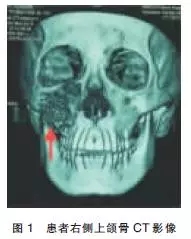

輔助檢查:2014-03-02在我院行CT提示右側(cè)上頜骨腫物,骨質(zhì)破壞明顯(圖1),于2014-03-07在全麻下行“右側(cè)上頜骨腫物探查術(shù)”?;颊哐雠P位,經(jīng)鼻插管全麻,常規(guī)消毒鋪巾,0.5%利多卡因+腎上腺素局部浸潤(rùn)。于右側(cè)上頜前庭溝注射麻藥時(shí)回抽有血,改變進(jìn)針?lè)较蚝徒嵌热曰爻橛醒?,遂?mL注射器穿刺抽出約5mL新鮮血液,考慮血管瘤可能。于右側(cè)上頜骨前庭溝作一約2.5cm切口,暴露腫物呈囊狀切開(kāi)骨膜后可見(jiàn)大量血液涌出,搔刮后未見(jiàn)實(shí)性瘤體組織,立刻嚴(yán)密縫合骨膜分層,縫合口腔黏膜。術(shù)畢,手術(shù)順利,麻醉滿意,手術(shù)歷時(shí)1h,出血量約100mL。